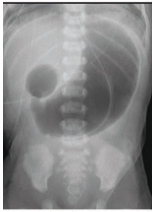

A 2-week-old boy has developed bilious vomiting. He was born via cesarean section at term. On physical exam, his pulse is 140, blood pressure is 80/50 mmHg, and respirations are 40/min. His abdomen appears distended and appears diffusely tender to palpation. Abdominal imaging is obtained (Figures A). Which of the following describes the mechanism that caused this child's disorder?